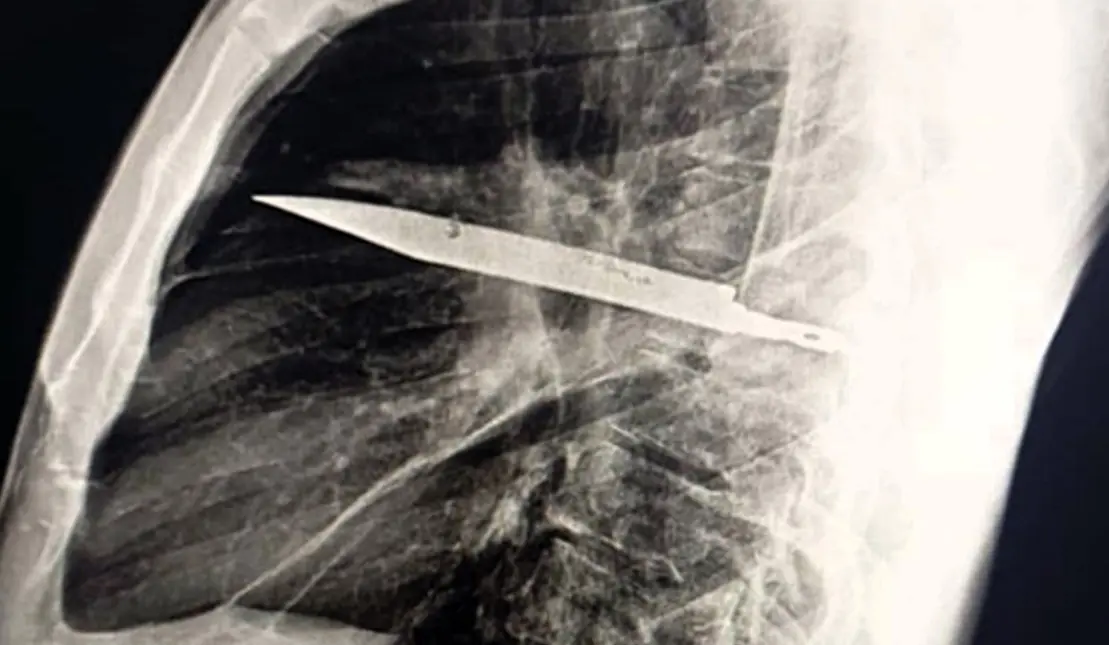

У Танзанії чоловік прожив 8 років із ножем у грудях і не здогадувався про це

У Танзанії 44-річний чоловік прожив вісім років із ножем у грудях, не звертаючись за медичною допомогою. Про це повідомляє Need To Know.

Рентген грудної клітки виявив справжню причину незвичних симптомів — всередині застрягло велике лезо ножа. Воно проникло через праву лопатку, дивом не зачепивши жодного з життєво важливих органів.Лабораторное оборудование

Під час операції хірурги обережно вилучили ніж, а також видалили гній, який з’явився через відмерлу тканину. Пацієнта перевели до відділення інтенсивної терапії, де він провів 24 години, після чого його перемістили до загальної палати. Там він перебував ще 10 днів під наглядом лікарів.